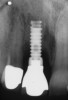

Figure 4  A pre-surgical periapical radiograph of the mandibular right peri-implantitis-affected first molar implant. (Photo reproduced with permission from the American Academy of Periodontology.) (Reference: Froum SJ. Regenerative treatment for peri-implantitis affected implant: a case report. Clinical Advances in Periodontics. 2012. Figure 5  [accepted for publication])

Figure 4

Figure 5  A 7-year post-surgical periapical radiograph showing the bone fill of the defect. (Photo reproduced with permission from the American Academy of Periodontology.) (Reference: Froum SJ. Regenerative treatment for peri-implantitis affected implant: a case report. Clinical Advances in Periodontics. 2012. Figure 13. [accepted for publication])

Figure 5